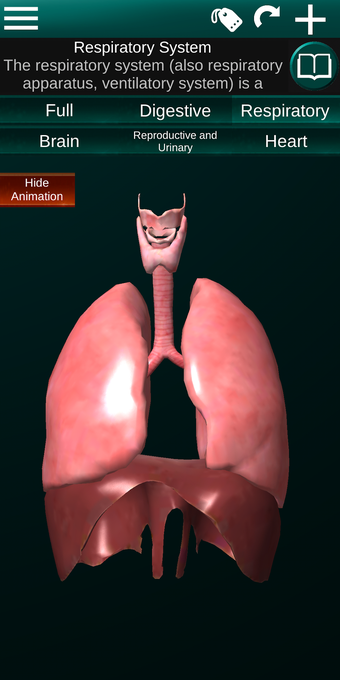

Diese Anwendung zeigt ein dreidimensionales Modell der menschlichen Körperorgane und eine Beschreibung aller von ihnen.

Sie können jedes Organ wie Herz, Gehirn, Lunge, Fortpflanzungssystem, Leber, Darm, Eierstock, Hoden, Magen, Niere usw. anfassen.

Sie können die App verwenden, um herauszufinden, welches die verschiedenen Körperorgane sind und welche Funktionen sie haben.